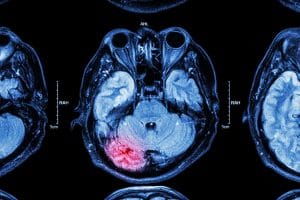

Surviving a car accident does not mean walking away unscathed. One of the most serious injuries is also one of the most misunderstood, and has some of the most dangerous results. Vehicle crashes are a leading cause of traumatic brain injuries (TBI), and the effects of those injuries can last a lifetime.

What causes traumatic brain injuries?

Any car accident has the potential to cause a traumatic brain injury if it happens at the right speed, the right force, and the right angle. While seatbelts make sure we are not ejected from our vehicles, we could still be subject to injuries sustained by slamming around inside our car or against any other passengers involved. More often than not, this leads to some form of TBI. Of course, anyone who is not wearing their seatbelt is at a higher risk for these (and other) injuries, which is why it is always recommended for anyone in any vehicle.